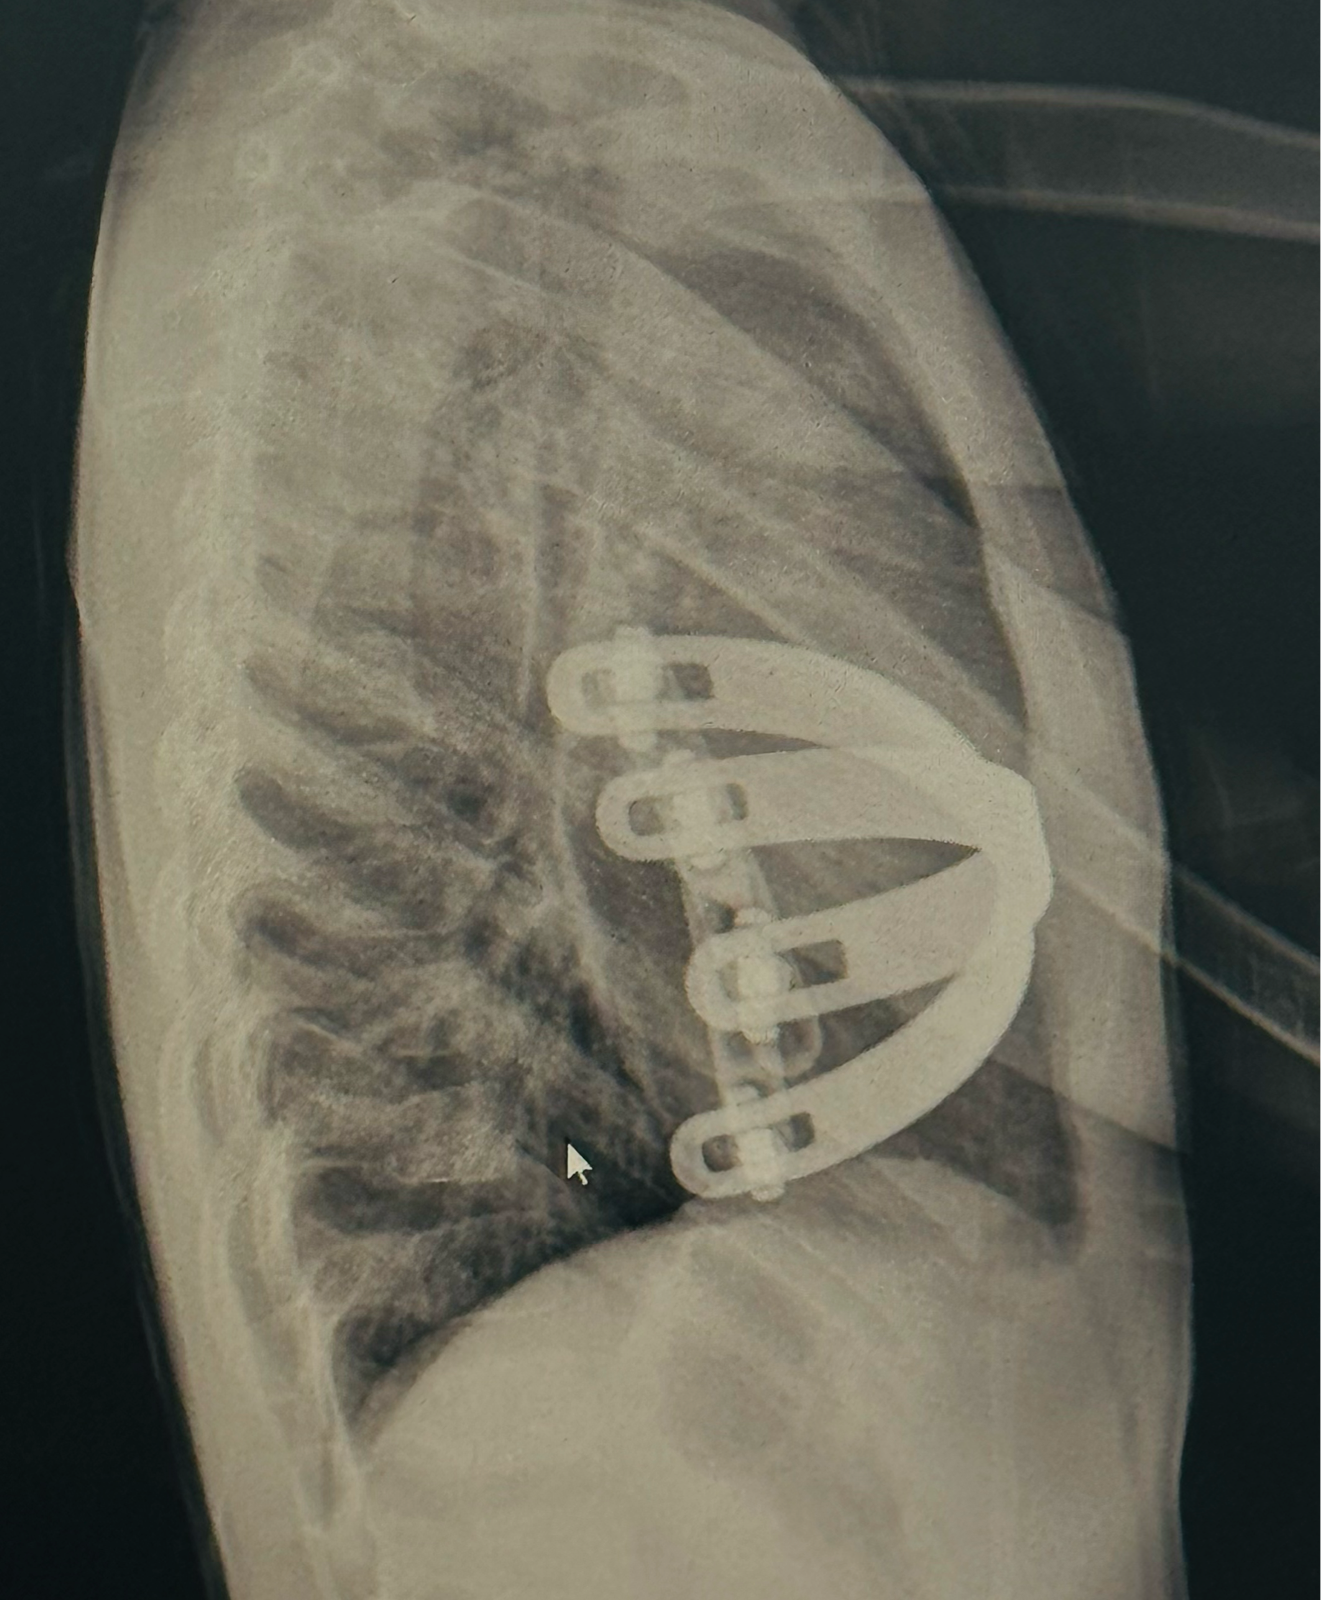

What Age Group Can Pectus Surgery Be Performed? Pectus surgery, particularly the Minimally Invasive Repair of Pectus Excavatum (MIRPE), can be performed in a wide age range, but it is most effective in children and young adults. The ideal age for intervention is between 6 and 14 years, when the chest wall remains pliable, and results are more predictable. However, adults can also benefit from surgery depending on the severity and symptoms of their condition. Early diagnosis and timely correction not only restore the chest’s physical appearance but also improve lung and cardiac function, boosting overall confidence and quality of life. This brave , a 8-year-old child who underwent MIRPE surgery for severe pectus excavatum at the age of 6years. The child had difficulty breathing during physical activity and noticeable chest depression. Following the procedure, the recovery was smooth, and the results were exceptional. Now, at 8 years of age ( 2 years post-surgery), the child is ready for bar removal with a beautifully corrected chest wall. The X-ray shows perfect bar positioning, achieving an ideal outcome. This case highlights the importance of early surgical correction, ensuring long-term success and improved well-being. Raise awareness for early treatment Contact Dr Rajkamal Vishnu Pectus Expert Pectus excavatum treatment in Chennai, Tamil Nadu Top pectus surgeon in South Asia Minimally invasive rib cage surgery India Best clinic for pectus deformity correction in Chennai Pectus excavatum surgery for children and adults in Chennai MIRPE surgery expert Tamil Nadu, India Rib cage disorder treatment center South Asia Chest wall correction surgery Chennai Affordable pectus surgery in India Bar removal after MIRPE in Chennai, Tamil Nadu